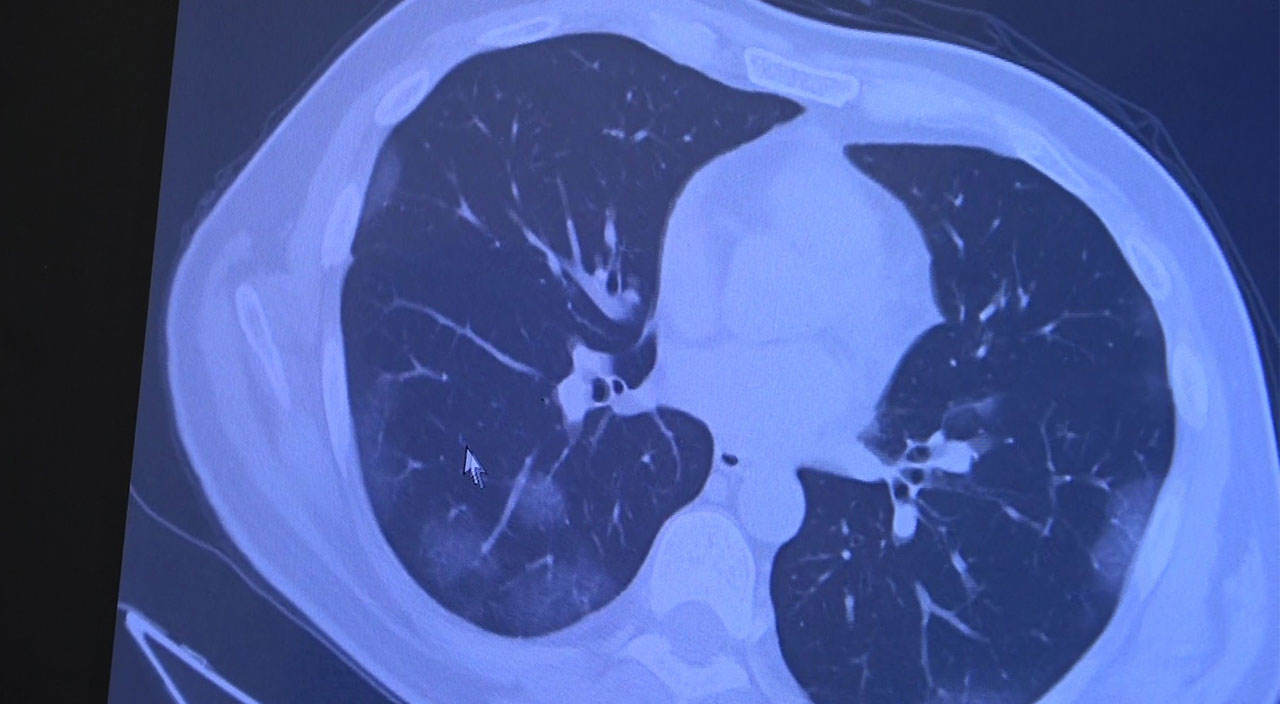

"Şu ana kadar gözlemlediğimiz hastalardan şunu söyleyebiliriz ki aşı olanlarda Omicron akciğere inmiyor. Bizim gördüğümüz en kötü tablo koronavirüsün akciğer tutulumu ile beraber ciddi akciğer hasarı, yoğun bakıma yatış ve ölümlerdi. Omicron gerçekten çok hafif seyrediyor. Şunu gönül rahatlığı ile söyleyebiliriz ki aşısızlarda hala akciğer tutulumu varken aşı olanlardan Omicron akciğerlere inmiyor. Ciddi anlamda aşılamanın devam etmesi ve hastalarımızın özellikle aşılarının tamamlamalarını istiyoruz. Üzerinden 3, 4, 5 ay geçmiş kişilerinin aşısız olduğunu kabul etmek gerekiyor. Virüs değişiyor, virüsle beraber toplum dinamikleri de değişiyor. O yüzden düzenli aşılarımızı yapmamız gerekiyor" diye konuştu.

Daha önce yapılan bir araştırmada, Omicron’un akciğerlere Delta ve daha önceki varyantlar kadar zarar vermediği ispatlanmıştı. Çalışmada yeni varyantın akciğerlerden çok boğazı etkilediği açıklanmıştı. University College London’daki viroloji profesörü Deenan Pillay, Omicron’un üst solunum yollarını, yani boğazdaki hücreleri daha fazla enfekte ettiğine dair açıklama yapmıştı. Öte yandan, akciğer dokularını enfekte etme becerisi olan bir virüsün ise potansiyel olarak daha tehlikeli ama daha az bulaşıcı olduğu belirtilmişti.